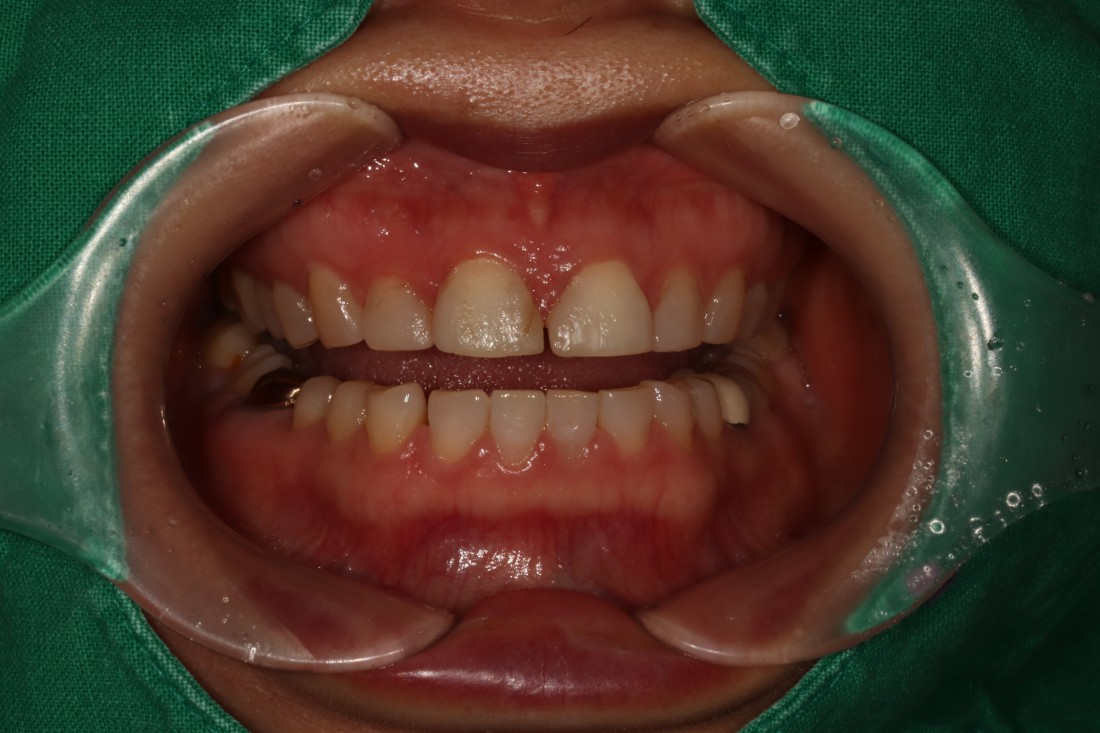

가끔 방송에 출연한 연예인 분들 중에

라미네이트가 굉장히 뭉툭하고

두껍게 제작된 분들이 보이는데요.

과거에는 치아 삭제량을 많이 해서

자연치아를 거의 남기지 않을 정도의

치아삭제가 이루어지기도 했습니다.

그러나 광주 무삭제 라미네이트는

치아삭제량을 최소화하고

미세가공법을 이용하여

0.2mm 머리카락 두께만큼 얇게

새로네이트를 제작하고 있기 때문에

자연치아같은 '자연스러운 아름다움'을

추구할 수 있습니다.